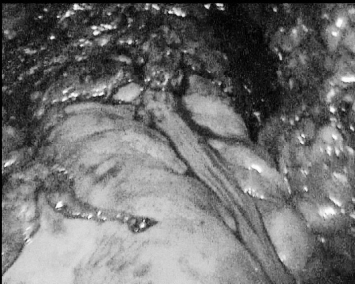

▲ 图3 膀胱、前列腺切除术后状态,创面无活动出血